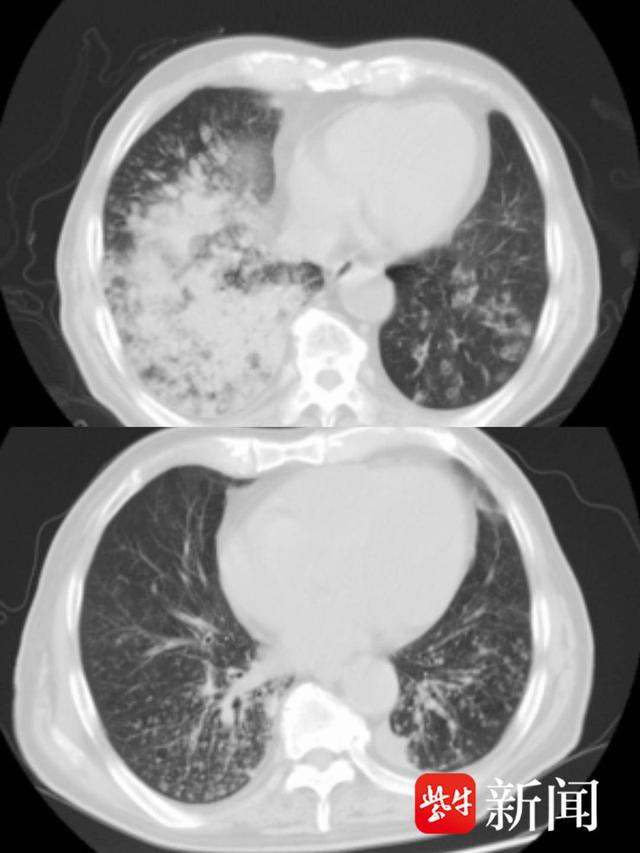

入院时,王老肺部有明显白肺。出院时间,白肺已经消失。

今年81岁的王老因咳嗽、气喘、高烧,被送至江都人民医院急诊,经查,患者指脉氧仅80%,胸部CT提示两肺有明显白肺,被收治在呼吸与危重症医学科RICU(呼吸重症监护病房)。

在医护人员的密切配合下,王老肺部的大量痰液被吸出,并成功取得所需肺泡灌洗液行NGS检测。结果显示为“肺炎链球菌及甲型流感病毒H3N2”混合感染,对症治疗后王老告别了咳嗽、气喘,影像结果显示白肺也已消失,王老于上周顺利出院。